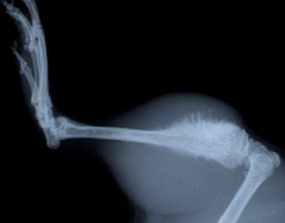

Рак костей

Рак костей — собирательное понятие. Сами по себе онкологические заболевания костей относительно редки — не более 1% всех случаев диагностированных опухолей. Но большая часть опухолей других органов метастазируют (проникают) в костную ткань. Врачи в таком случае говорят о вторичной опухоли костной ткани, и только в этом случае врач может дать ответ, откуда развилась опухоль кости.